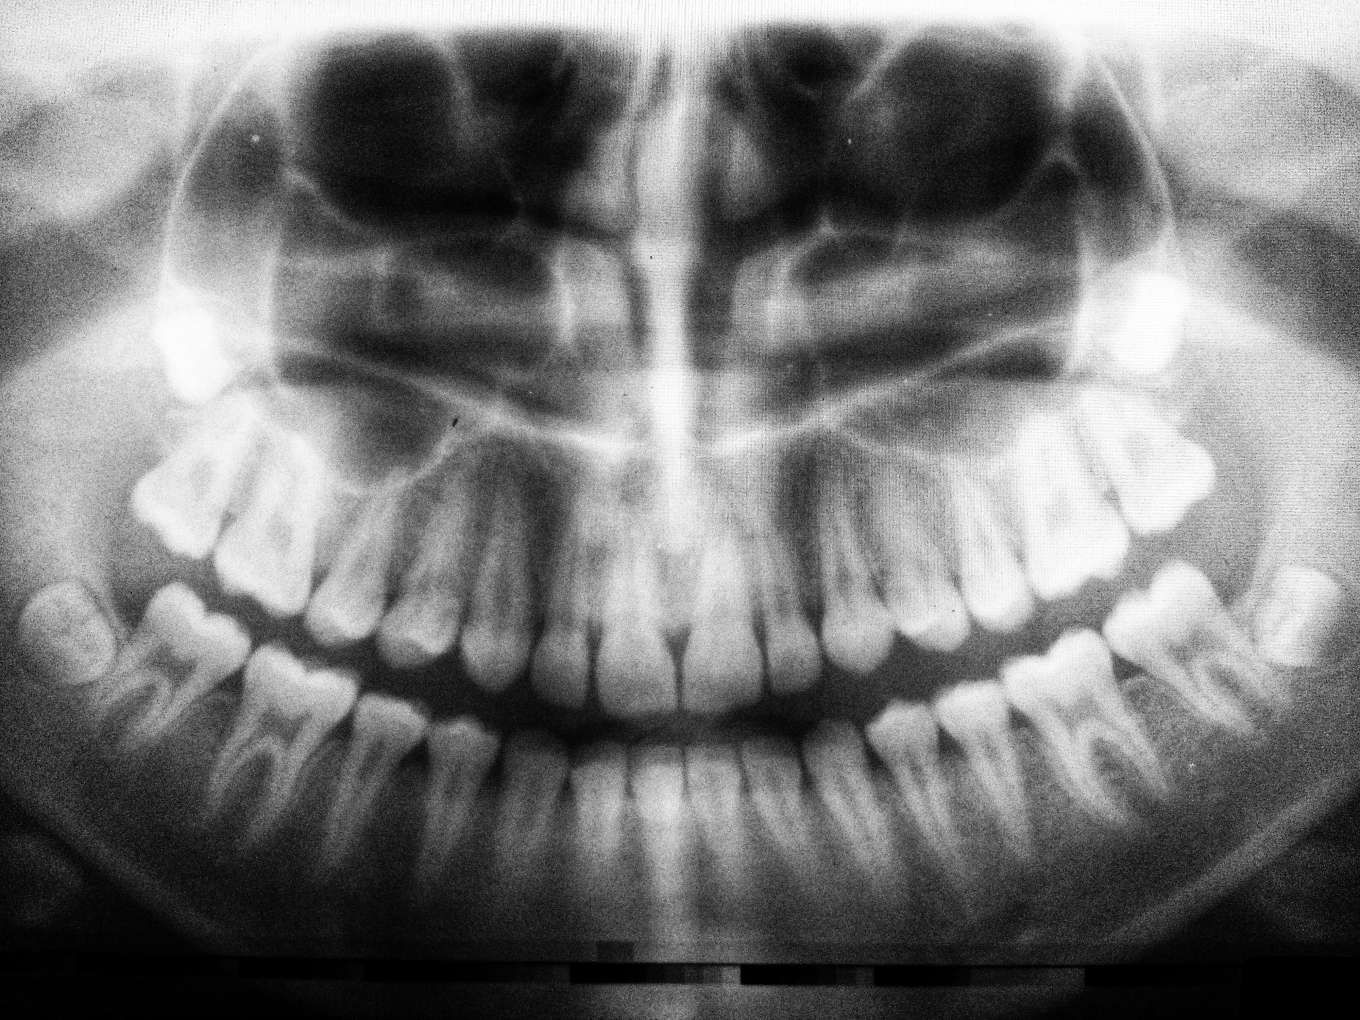

또한, 3D-CT와 같은 첨단 디지털 장비는 눈에 보이지 않는 잇몸뼈의 상태나 보철물 하방의 문제까지 정밀하게 파악하여 진단의 정확도를 높입니다. 가까운 치과에 내방하셔서 현재 구강 상태를 반드시 확인해보세요.